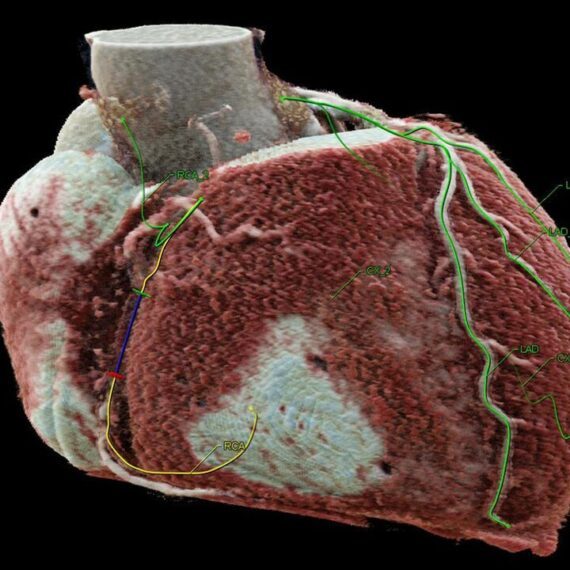

- Автоматическая сегментация коронарных окклюзий, определение и цветовое кодирование центральных линий.

- Цветовая кодировка указывает ракурс сегмента сосуда. Это позволяет выбрать оптимальный угол сегмента поражения, который обычно не виден на рентгенограмме до фактического начала процедуры.

- Кодированные цветом центральные линии используются для регистрации во время процедуры. Таким образом, требуется меньше ангиографических изображений.

При интервенционном вмешательстве CTO syngo CTO Guidance упрощает процедуры позиционирования проводника, обеспечивая параллельный (рентгеноскопические и КТА изображения) контроль. Дополнительная информация, такая как данные о кальцификации и истинная длина областей тромбированных сосудов, помогает правильно выбрать проводник, ориентацию и успешно провести операцию.